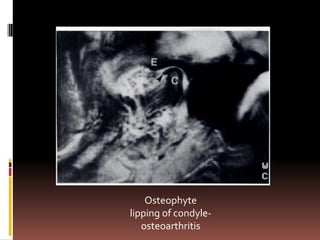

Osteophyte

lipping of condyle-

osteoarthritis